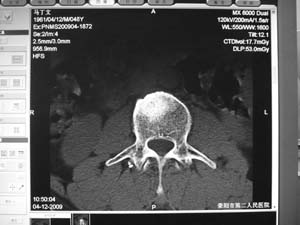

标题: MRI2131:男,腰痛三月向右下肢放射一月余 [打印本页]

标题: MRI2131:男,腰痛三月向右下肢放射一月余

骨质轻微破坏,硬化明显,椎管未见异常,考虑良性骨瘤的可能性大,

椎体增生 硬化 囊变。考虑:退变!

椎体前缘骨质增生硬化、囊变。椎旁软组织未见确切异常。考虑椎体前缘软骨结节。

1)l3椎体前上缘许莫氏结节形成。2)腰椎退行性改变。

l2大部分椎体信号增高-----脂肪变性,转移待排。l3 椎体t2 低信号考虑硬化增生。

腰3椎体骨样骨瘤.